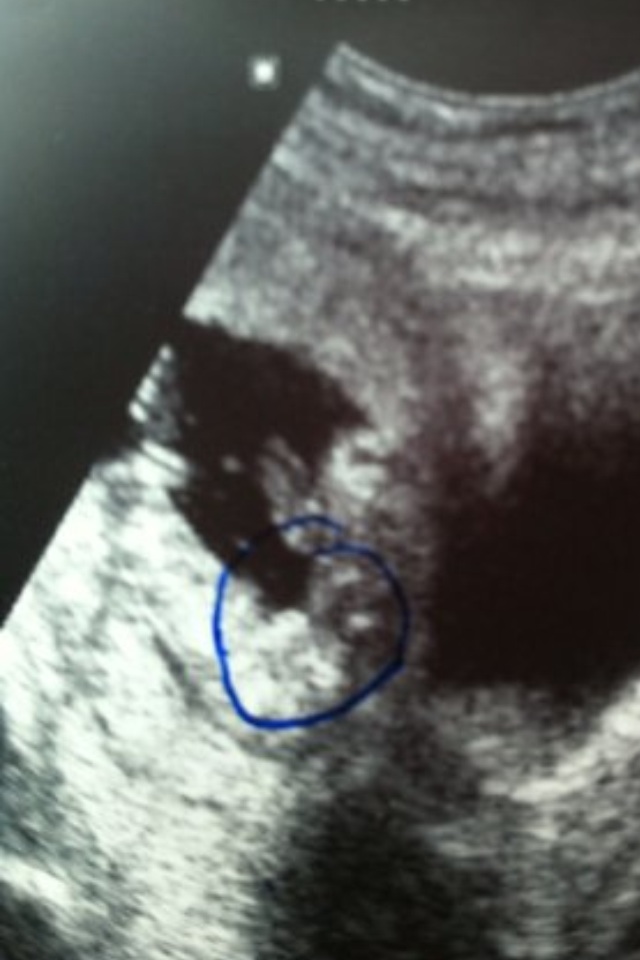

16 week ultrasound-swayed girl